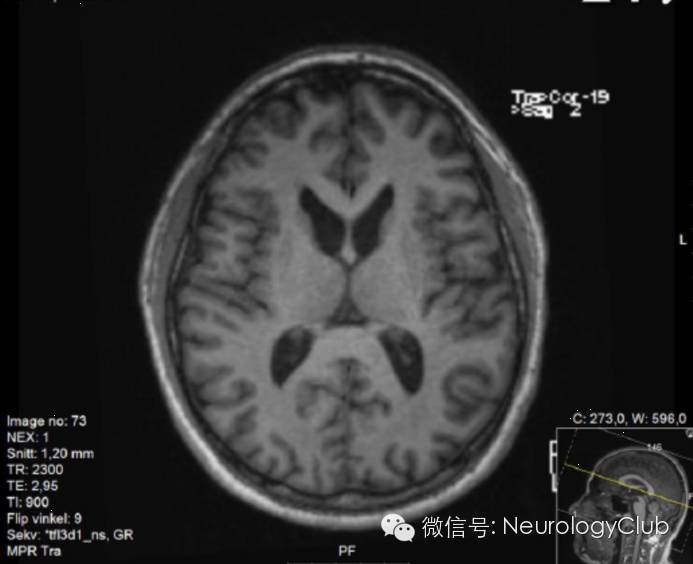

39岁男性,因“人格改变,不自主运动与进食困难”就诊。查体发现进食性肌张力障碍,构音障碍,肢体肌张力障碍以及舞蹈样动作(视频)。血清转氨酶和肌酸激酶水平升高。血涂片可见棘红细胞,肌肉活检提示肌病,影像学检查提示尾状核萎缩(图1-4)。蛋白质印迹法提示chorein蛋白缺失,遗传学检测发现复合杂合子新的VPS13A基因突变(c.266dupT以及外显子52,53,55和58缺失),确诊为舞蹈病-棘红细胞增多症。患者接受颏舌肌肉毒素注射治疗,进食和讲话症状明显改善。

(图4:横断面T1WI可见尾状核明显萎缩)